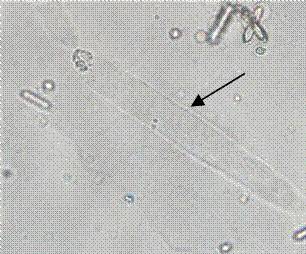

2015510 |

| 粘液丝 |